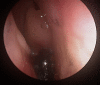

A woman in her late 70s with chronic bilateral epiphora under ophthalmology review was referred to our department for dacryocystorhinostomy after punctoplasty and detection of nasolacrimal duct obstruction. A CT scan of the paranasal sinuses for preoperative planning revealed complete opacification of the right maxillary, anterior ethmoid, frontal and sphenoid sinuses, left septal deviation and an incidental finding of foreign bodies in the right anterior nasal airspace. She proceeded with functional endoscopic sinus surgery (FESS) and removal of foreign bodies. To our surprise, a partially eroded 20 pence and 1 penny coin were found and removed from her right nasal airway. There was no history given about foreign bodies in her nose. Her symptoms improved postoperatively.